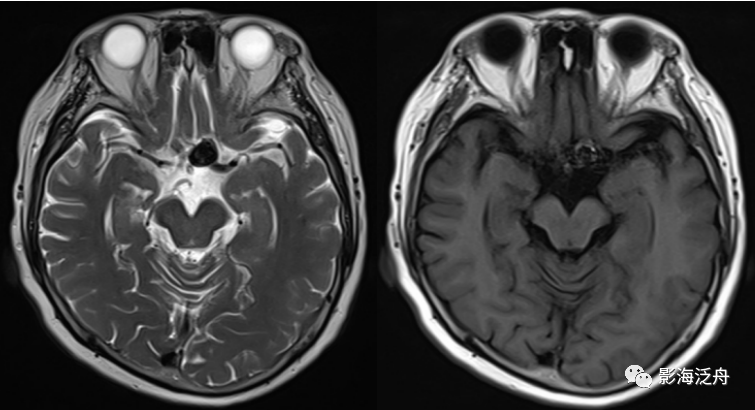

病例二:患者女,78岁,头晕1周,无头痛、恶性呕吐等症状,既往有胃CA手术史和糖尿病、高血压等病史。

病例二:左侧前交通动脉动脉瘤。动脉瘤瘤体显示清晰,呈流空改变,内见斑片状T2WI稍高信号影,可能是湍流造成的。如果脑子里完全没有去观察颅内血管的意识,那就很容易漏诊。